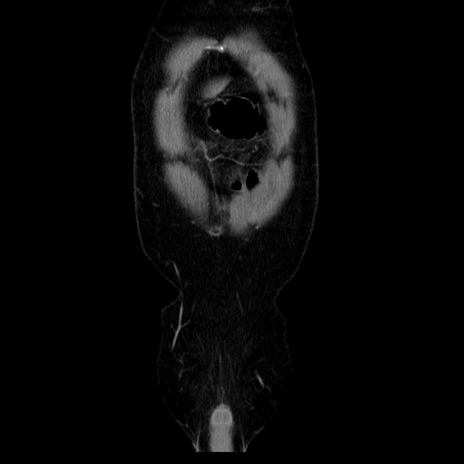

横断像

【症例】40歳代男性

【現病歴】2日前から胃痛あり。徐々に周期的な激痛に変化した。本日になっても激痛があるため受診。

【身体所見】意識清明、BT 38-39℃台あり、腹部:膨満、やや硬、右下腹部に圧痛あり。

【データ】WBC 8500、CRP 23.26